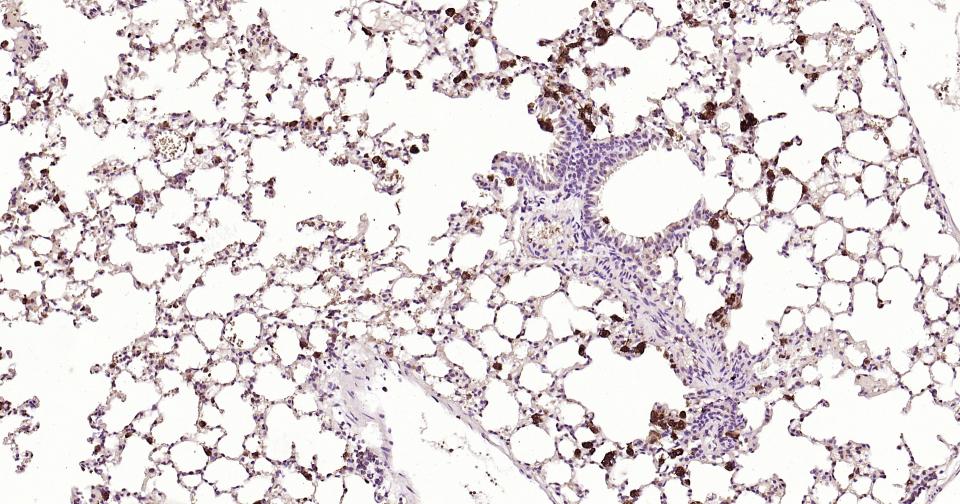

| IHC-P | Human, Mouse, Rat | 1:100-500 | |